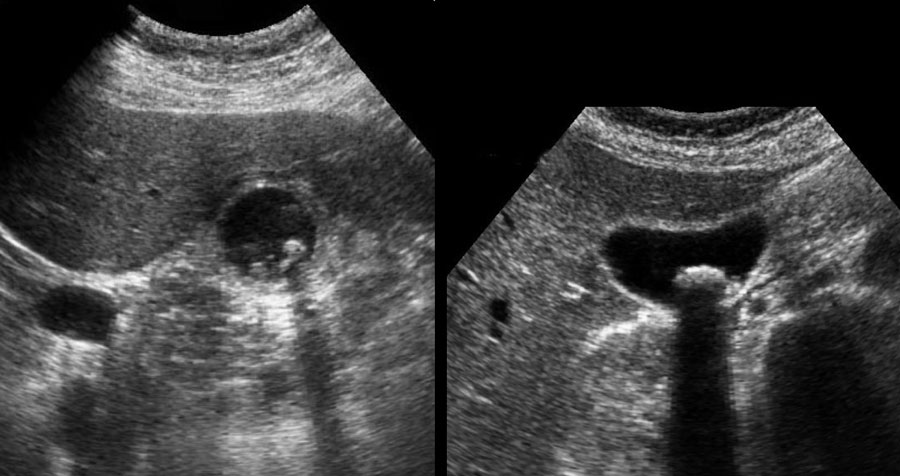

Hình ảnh siêu âm của một bệnh nhân bị phình to túi mật cấp tính, được khảo sát trên mặt phẳng dọc và mặt phẳng ngang.

Sỏi gây tắc nghẽn đang ở trạng thái kẹt (mũi tên).

Lưu ý rằng khi ấn đè, túi mật phình to phồng lên về phía thành bụng (đầu mũi tên), cho thấy áp lực trong lòng túi mật tăng cao.